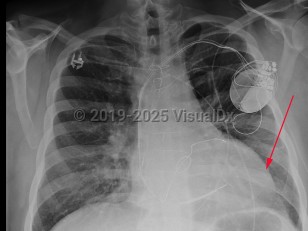

Chest pain, Pleural effusion, 50-59 year old Female

Pleural effusionPleural effusion

Hemothorax